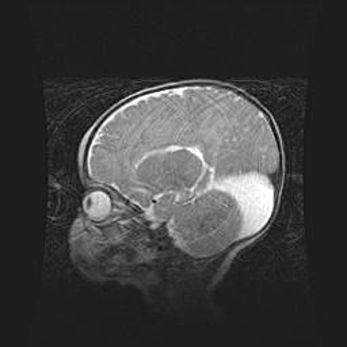

Множественные кисты обоих полушарий головного мозга, наибольшая из них в правой затылочной области. Ассиметричная атрофическая гидроцефалия.

Возраст: 7 месяцев

Вес: 5660 г

Пол: мужской

Окружность головы: 41,5 см

Срок гестации: 28-29 недель

Кисты головного мозга развиваются в результате многоочаговых некрозов вещества мозга и возникают вследствие перенесенной перинатальной инфекции, менингитов, энцефалитов, асфиксии, родовой травмы, расстройств мозгового кровообращения различного генеза. Образованию кист в веществе головного мозга плодов и новорожденных способствуют такие факторы, как высокое содержание в нем воды, недостаточная (или отсутствие) миелинизация и слабая астроглиальная реакция на повреждение.

Кисты могут сочетаться с гидроцефалией и другими поражениями головного мозга.